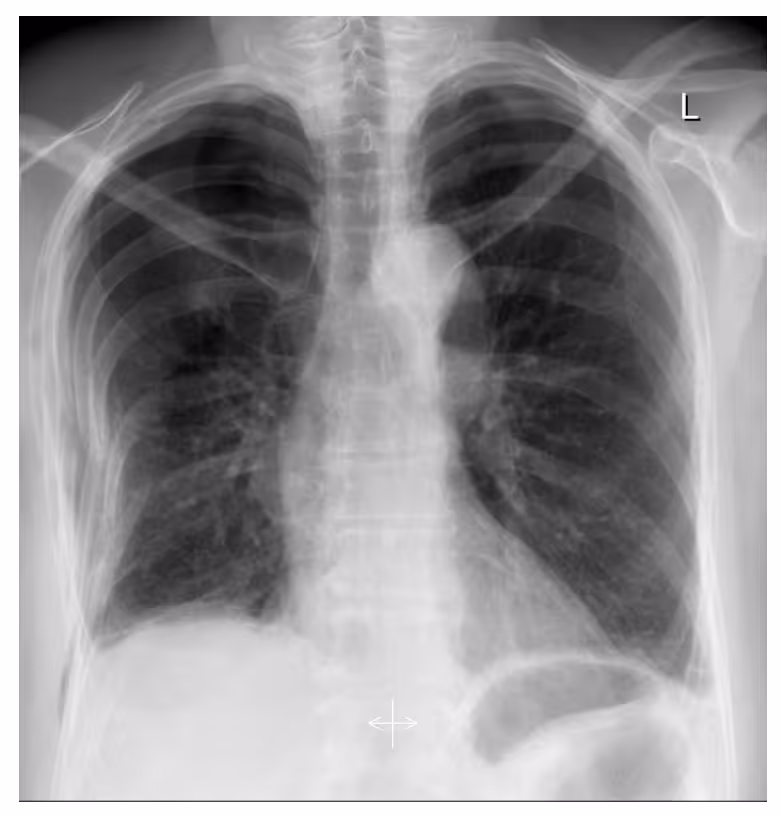

- A 55-year-old female toppled to the right side experiencing thoracic tenderness and mild shortness of breath.

- Image findings:

- Partially displaced rib fractures and a pneumothorax on the right side.

- Fractures of the right ribs 3-8 were obvious with a displacement of the 5th and 6th ribs.

- The thin pleural line and the lack of the pulmonary vessels in the right apex visibly reflect a pneumothorax.

- Subcutaneous emphysema of the thoracic wall.